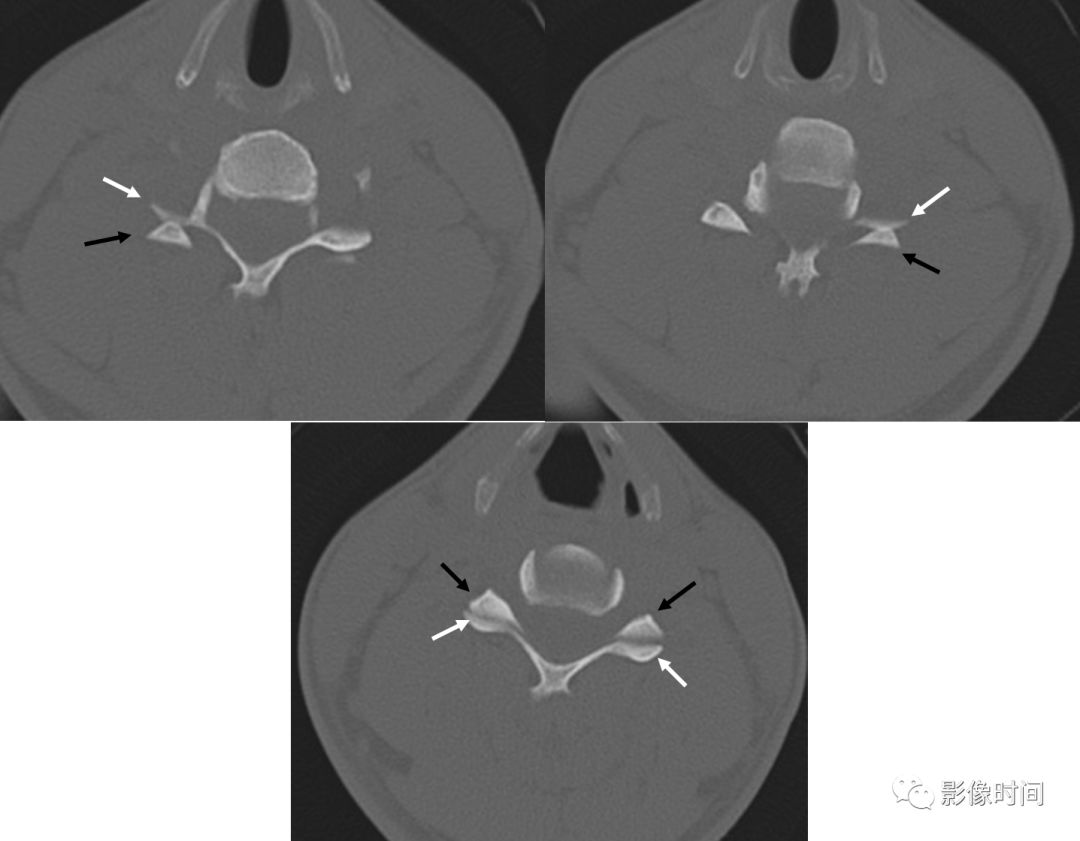

2裸面征

裸面征(naked facet sign),又称反汉堡面包征(reverse hamburger bun sign)

当脊椎小关节脱位时,上关节突脱位可位于上关节突后方,关节面向下显露,表现为关节面裸露,为裸面征(黄箭)。脱位可单侧或双侧出现;本例为左侧脱位,右侧为半脱位:可见上关节突(红箭)外移,相对下关节面显露,表现为关节面部分裸露(白箭之间)。

这是屈曲分离型损伤的特点,提示有严重的韧带损伤和脊柱不稳。

上图为 45 岁男性,交通事故后行轴位 CT 检查。显示右侧颈椎汉堡包征异常。双侧关节突不同程度分离、移位。

典型病例

正常汉堡包征的小关节(下图);外伤后,CT 骨窗示其前部「面包」(上关节突,黑箭)后移,位于下部「面包」(下关节突,白箭)的后方,关节面裸露。

引用自:https://radiopaedia.org/articles/naked-facet-sign-vertebral-column